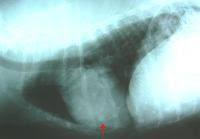

Clinical Rounds Canine Thyroid Carcinoma In 4 Year Old American Bulldog from cdn.sanity.io Since i no longer have a thyroid, i have to take hormones that control my metabolism, blood calcium, and energy levels. We have provided some more information about cancer. Sometimes doctors find neck lumps during a physical exam. Cancer was changing me for the better and showing me how strong i truly am. How long do they keep a dog in the pound before they put him down? If you're wondering, does my dog have cancer? this might be a scary time for you. I'm experiencing this with one of my dogs, a ten year old terrier, right on the heels of losing my other terrier to cancer. Can he really smell cancer even if he isn't trained for it?

Lymphoma is a common blood borne cancer in dogs and cats. Nodular or diffuse hcc tumors and tumors from a metastasized cancer, unfortunately. Whereas we used to expect our pets to die of renal or. I don't have a thyroid anymore. How to tie a double hoop belt. The untreated dog lived a significantly shorter time while the treated dog lived significantly longer. Cancers result from accumulation of mutations over y. Deteriorations in the pet may occur suddenly. How long does someone live with leuukemia? How long dogs can live with a bladder cancer diagnosis. Dozens of therapy dog organizations across america offer visits. Most thyroid cancers are found when patients see a doctor because of new neck lumps (called nodules). If untreated, a dog with cancer can.